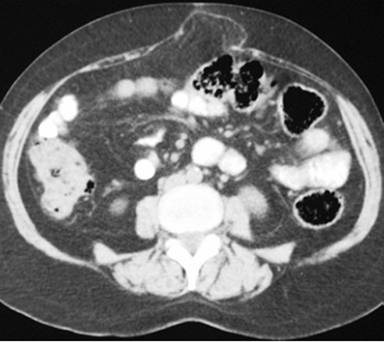

The diagnosis of pancreatic pseudocyst was highly probable but, considering the uncommon chronic presentation, and, in order to measure amylase, tumor marker CA 19-9 and carcinoembryonic antigen levels (CEA) in the cystic fluid, an image-guided puncture was planned. To demonstrate possible communication between the pseudocyst and the main pancreatic duct, an endoscopic retrograde cholangiopancreatography (ERCP) was planned as well but, since the patient was reluctant to undergo both procedures, surgical drainage was carried out instead. Since the pseudocyst appeared to be adherent to the posterior gastric wall on CT scan, a cystogastrostomy was scheduled. At laparotomy, by means of an anterior gastrotomy and a 5 cm incision using electrocautery at the posterior gastric wall, where the bulging pseudocyst was visualized, abundant non-viscous clear brownish fluid was drained immediately. A fluid sample and pseudocyst wall biopsy were sent for determination of amylase level and histopathological exam. The amylase fluid level was 8,524 IU/L. The cystogastrostomy was completed using a running 2-0 polypropylene suture. The anterior gastrotomy was sutured as was the abdominal wall. Both frozen section and definite histopathological examination demonstrated fibrous tissue, with no epithelial lining, epithelial tissue or malignant transformation. With an uneventful recovery, the patient was discharged 10 days after surgery. At follow-up 12 months later, an abdominal wall protrusion was noted upon exertion. An abdominal wall defect was palpated at the surgical scar. A control CT scan demonstrated a midline abdominal wall defect, but no evidence of a pancreatic pseudocyst (Figures 2 and 3). Incisional hernia surgery was performed. Six months after this latter surgery, the patient remains in good condition.

Figure 3. Midline abdominal wall defect with partial protrusion of the omentum. |